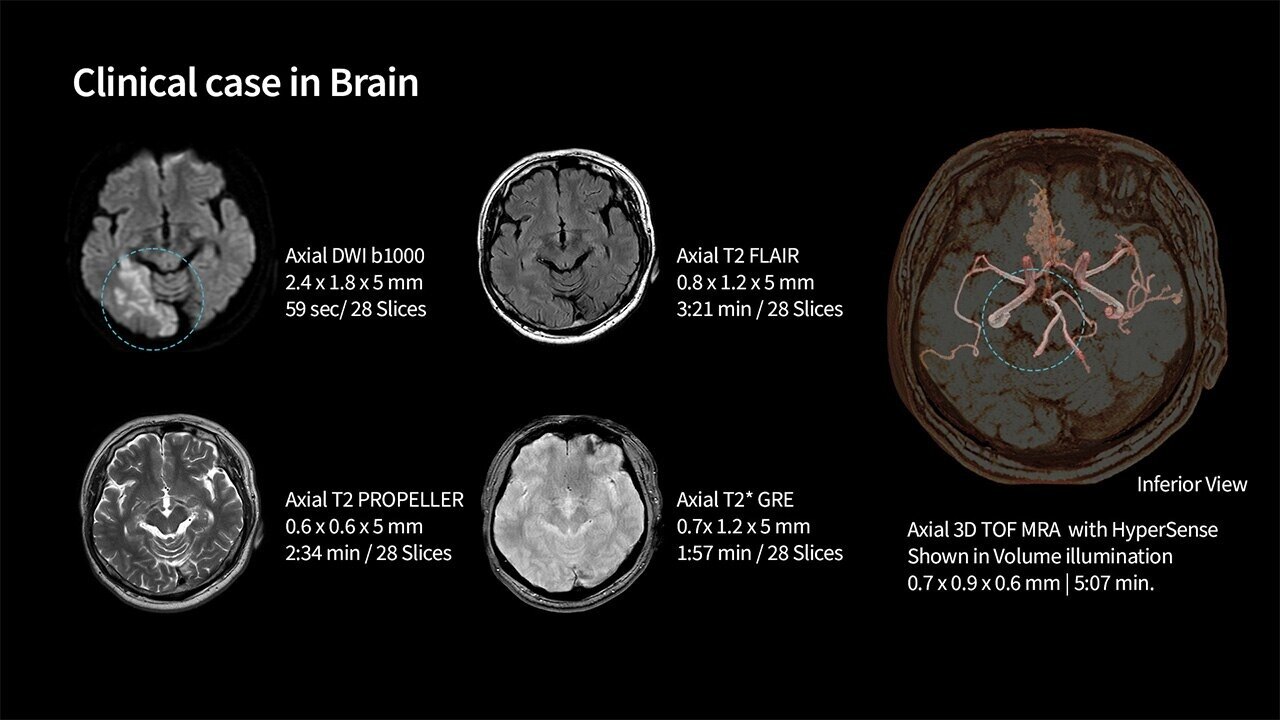

With SIGNA™ Prime, you don’t have to choose between accessibility and quality. We equipped SIGNA™ Prime with state-of the-art Total Digital Imaging (TDI) 2.0 technology. We paired that with the latest AI technology to generate images that are as easy to read as the system itself is to use. SIGNA™ Prime includes AIR™ Recon DL capability, the industry’s leading deep learning-based image reconstruction algorithm that works across all anatomies. AIR™ Recon DL improves image quality at the foundational level by leveraging raw data to remove image noise and ringing. It also improves SNR and image sharpness, enabling much shorter scan times.